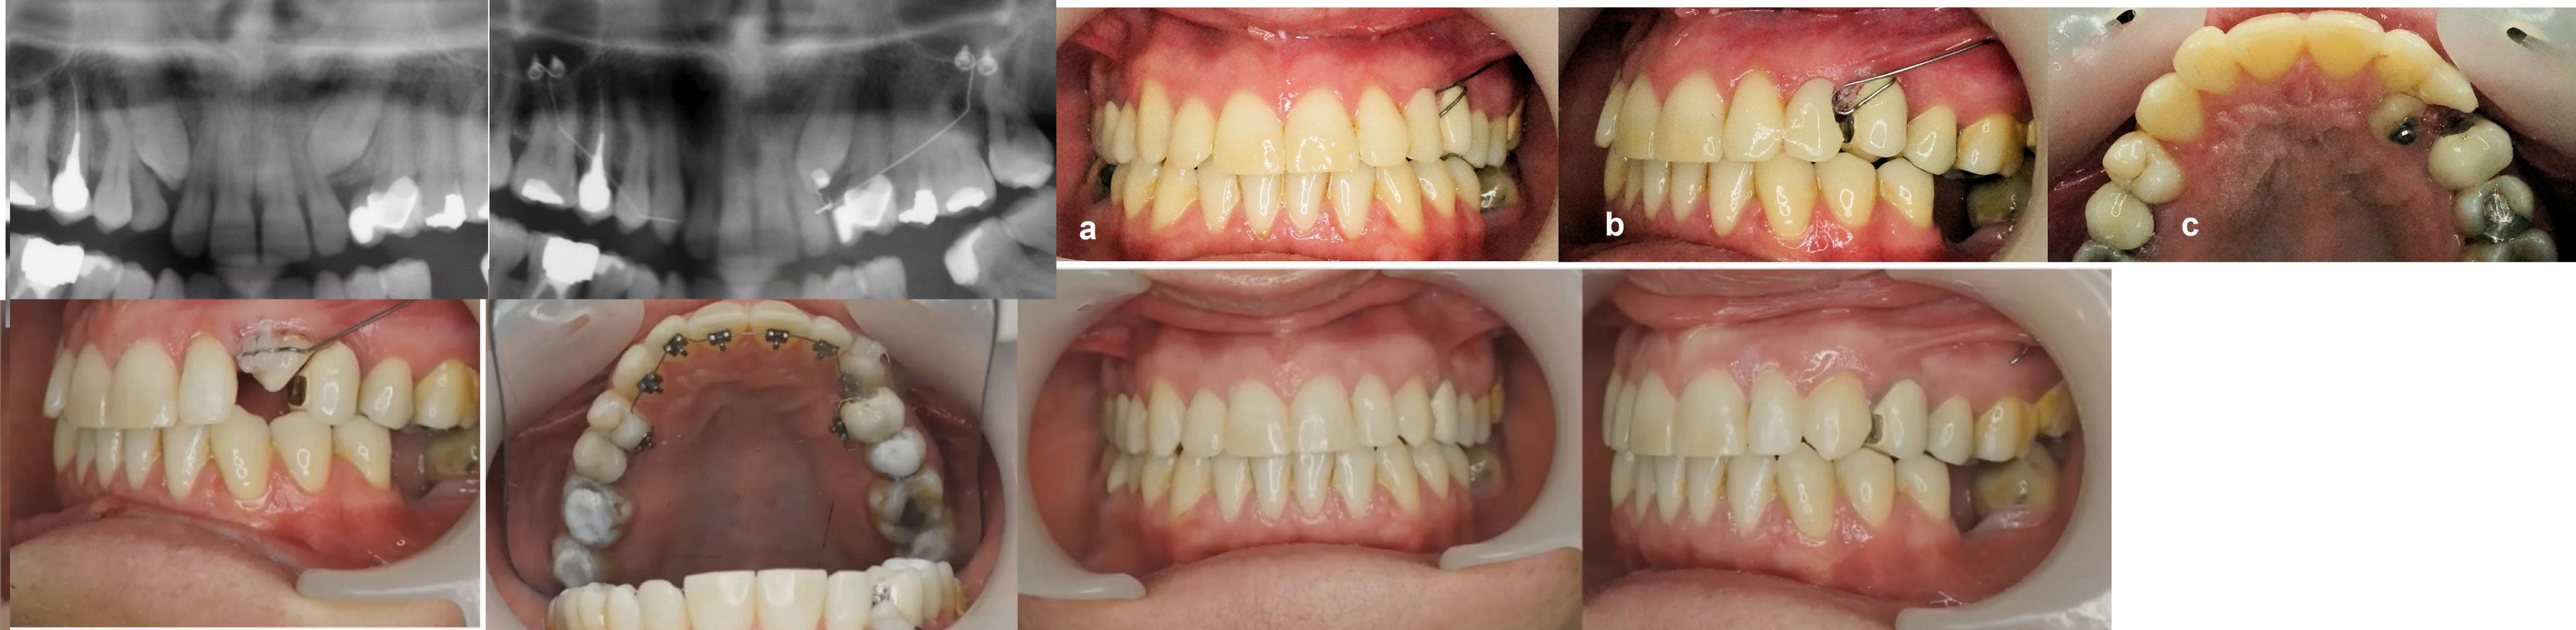

Exemple de traction discrète de canines chez une adulte. Système CT8.

Dans le cas présenté ici, la mise en place totale de la canine depuis son collage a bien duré 4 ans.

Cependant, la traction elle-même ne gêne quasiment pas le patient, et dans tous les cas un éventuel traitement orthodontique complémentaire est beaucoup plus court car on ne le démarre que lorsque la canine a bien progressé.

> Exemple de traction discrète de canines chez une adulte. Système CT8.

Mouai… ok dans le cas que tu montres, parce qu’il y a un cantilever qui maintient l’espace…. Et encore! 4 ans d’une vie d’humain à se faire suer, c’est beaucoup. Surtout quand l’alternative prend 4 fois moins longtemps.

Tu dis des bêtises, bouboule, regarde un peu mieux et essaie de comprendre ce qui a été réalisé :

Tu verras qu'il n'y pas eu de "cantilever pour maintenir l'espace" , que la canine incluse de l'autre côté n'a pas été extraite et qu'au final les 2 canines sont en place et sont fonctionnelles.

La partie orthodontie (en lingual), limitée à la phase de finition, a duré moins de 20% du temps global de traitement.

Pour en revenir au cas, la traction a été faite tout naturellement avec un CT8.

Ce système simplifié CT8, limité à une « canne à pêche » fixée sur 2 microvis placées en fin de vestibule dans le processus zygomatique représente un véritable changement de paradigme du traitement des canines.

La finition a été ici réalisée uniquement avec un fil NiTi léger passé dans des attaches en résine composite photopolymérisées extemporanément.